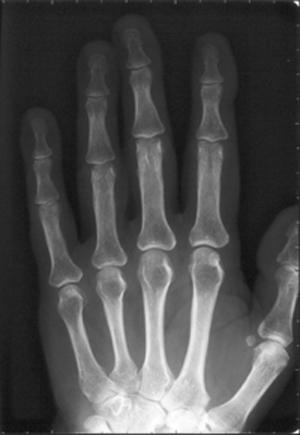

On peut comparer la qualité de l’image et le nombre de détails visibles avec la radiographie historique de la main de l’épouse de Röntgen effectuée en 1895 (voir Figure 4 du 1er article du dossier « Histoire de la découverte des rayons X et de leur application en médecine »)

Radiographie osseuse |

Tous les os. Douleurs, gonflements, craquements, blocages. Pathologies recherchées : Fracture. déviation, infection, tumeur. |

|